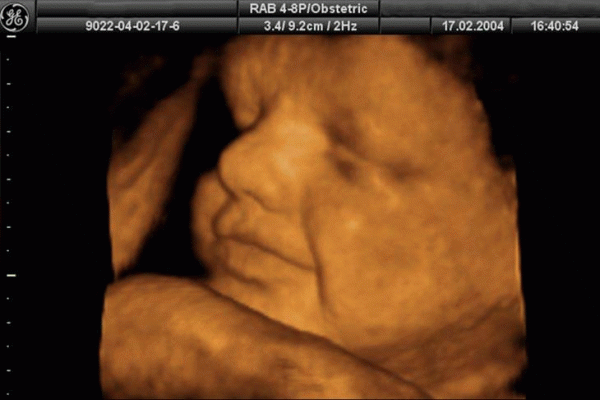

Siêu âm

dấu hiệu thai nhi bị dị tật

Siêu âm giúp phát hiện sớm các dấu hiệu thai nhi bị dị tật.

Công nghệ siêu âm sử dụng sóng âm thanh tần số cao để tạo thành hình ảnh của thai nhi trên màn hình máy tính. Siêu âm thường được thực hiện với hầu hết các thai phụ bởi siêu âm có thể dự đoán ngày sinh, kiểm tra sức khỏe tổng thể, sự phát triển, giới tính và vị trí của em bé, đo lượng nước ối và kiểm tra tình trạng của nhau thai. Qua đó, các biến chứng của nhau thai như nhau thai thấp hoặc dị tật như hở vòm miệng có thể được phát hiện.